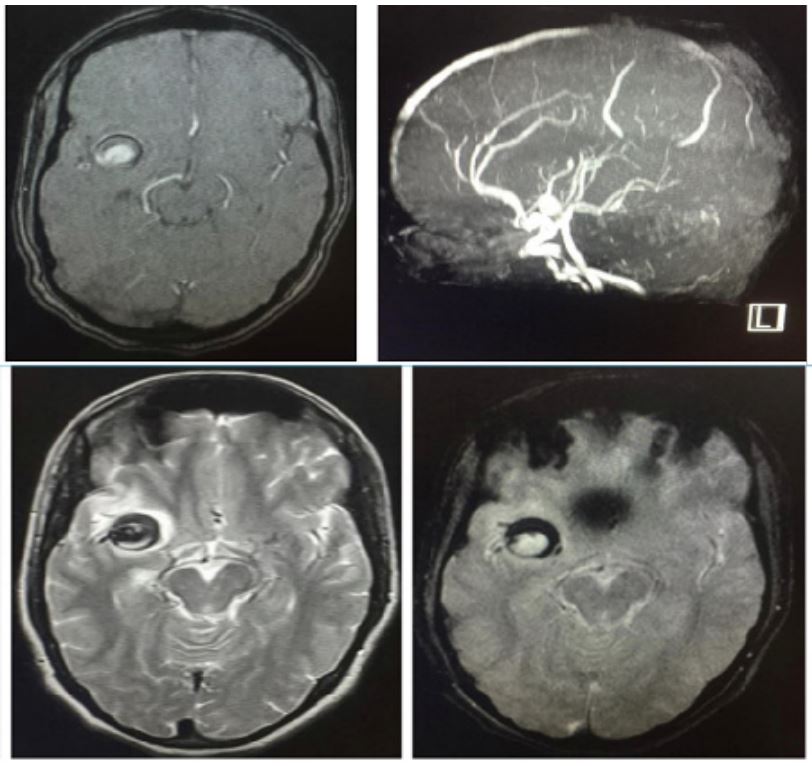

MRI brain done along with MR Angiography-Showed a T2/FLAIR hyperintensity with diffusion restriction in DWI noted right frontal and right gangliocapsular region (Figure 1 marked in red arrow) along with partially thrombosed aneurysm of size 1.8 cm x 1.7 cm arising from M2 segment of Right middle cerebral artery (Figures 2 and 3). Then patient undergone 4 Vessel Doppler of neck and echocardiography, as it showed no evidence of thrombi. Then Serum homocysteine, serum ANA. APLA profile done. USG abdomen screening done for ADPKD. All investigations are within normal limits. So final diagnosis Spontaneous Thrombosis of Unruptured intracranial aneurysm causing acute infarct presenting as isolated Left UMN facial palsy. Neurosurgery opinion obtained as it was spontaneously thrombosed non giant intracranial aneurysm with acute infarction advised to start antiplatelet therapy and watch for any evidence of rupture. After 6-month follow-up, MRI taken aneurysm completely thrombosed and advised to continue antiplatelet therapy.

Figure 1: MRI brain done along with MR Angiography-Showed a T2/FLAIR hyperintensity with diffusion restriction in DWI noted right frontal and right gangliocapsular region (marked in red arrow).

Figure 2 & 3: MRI Along with partially thrombosed aneurysm of size 1.8 cm x 1.7 cm arising from M2 segment of right middle cerebral artery.